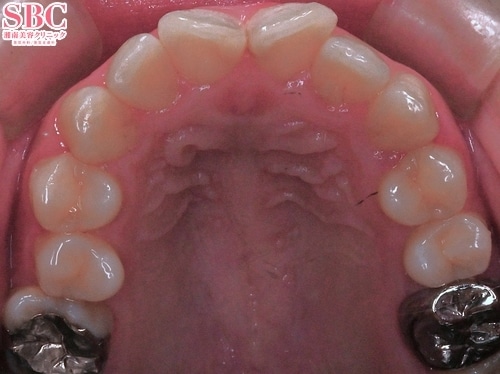

施術後13ヶ月後

奥歯のアーチが狭く、当初は見える歯の本数が少なかったですが、

矯正後は白く並ぶ歯がより見えるようになり、見違えるほどきれいになりました^^!!